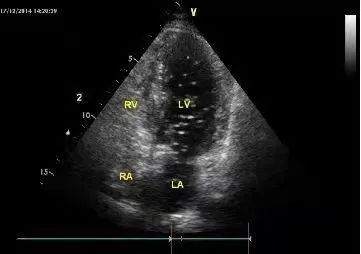

超声右心声学造影检查目的通俗地讲,就是如果左、右心系统存在异常通道(如卵圆孔未闭、房间隔缺损、肺动静脉瘘等),那么注入造影剂后左心腔会出现不同程度的微泡显影,也因此能轻松找到异常通道原因。生理盐水微泡造影剂制备简单、操作简单、经济安全、几乎无副作用。造影操作简单、无创、无痛,检查时间短,可重复性高,检查前无需特殊准备,近些年备受临床关注,并得到了广泛的应用。

超声右心声学造影是经外周静脉注射手震微气泡生理盐水造影剂,使右心系统显影,根据显影顺序、途径和时间对某些结构和血流异常作出诊断和鉴别诊断。一般通过静脉注入振荡的无菌生理盐水注射液,使右系统显影,再通过联合超声心动图检查,就可以进一步了解右心系统各腔室的解剖和血流状况,协助确定有无心腔内(卵圆孔未闭、房间隔缺损等)或心腔外(肺动静脉瘘)的右向左分流。